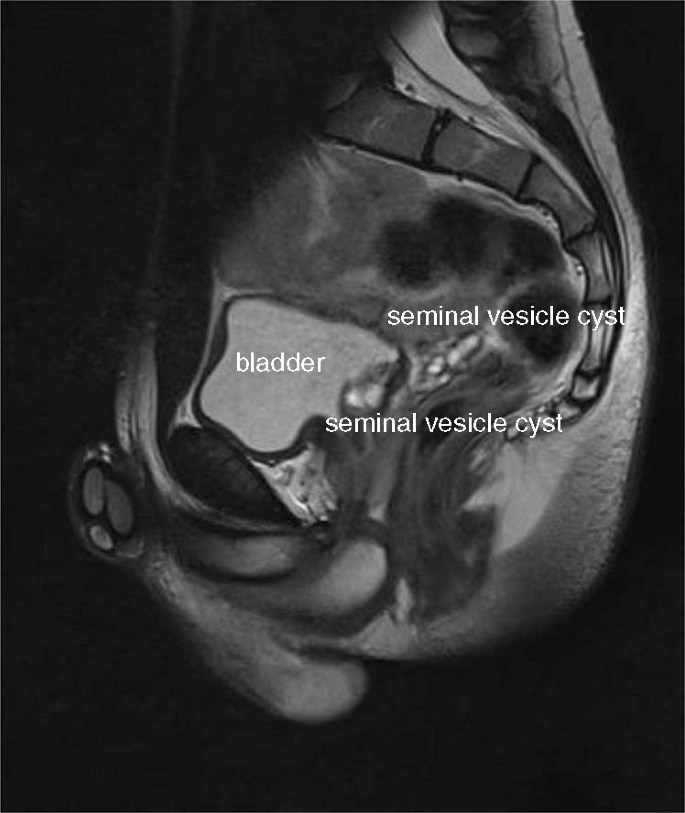

An 18-year-old male patient was referred to our institute because of recurrent macrohematuria. Physical exploration and laboratory evaluation were without pathological findings. Renal and vesical ultrasound showed renal agenesis on the left side and a solid appearing mass in the retrovesical space (3.5 × 1.4 cm). ZS was suspected. Magnetic resonance imaging (MRI) confirmed the presence of enlarged seminal vesicles with intraluminal proteinaceous or hematic content in the retrovesical space on the left-hand side (see Fig. 1). The left kidney was missing, and a residual ureter was visible.

The suspected diagnosis of ZS is usually confirmed by MRI [4]. Seminal vesicle cysts appear as hyperintense on T2-weighted images and as hypointense on T1-weighted images. Seminal vesicle cysts need to be differentiated from other pelvic cystic lesions such as Müllerian duct cysts or utricular cysts. Differentiation is based on the position of the cysts in relation to the bladder neck. Utricular cysts communicate with the urethra, whereas Müllerian duct cysts do not. Müllerian duct cysts have normal seminal vesicles and ejaculatory ducts; anatomically, they are based on the midline. Wolffian ducts cysts, which are present in ZS, are located in the paramedian area [1, 4, 11]. In addition, EDO can be verified by means of MRI.